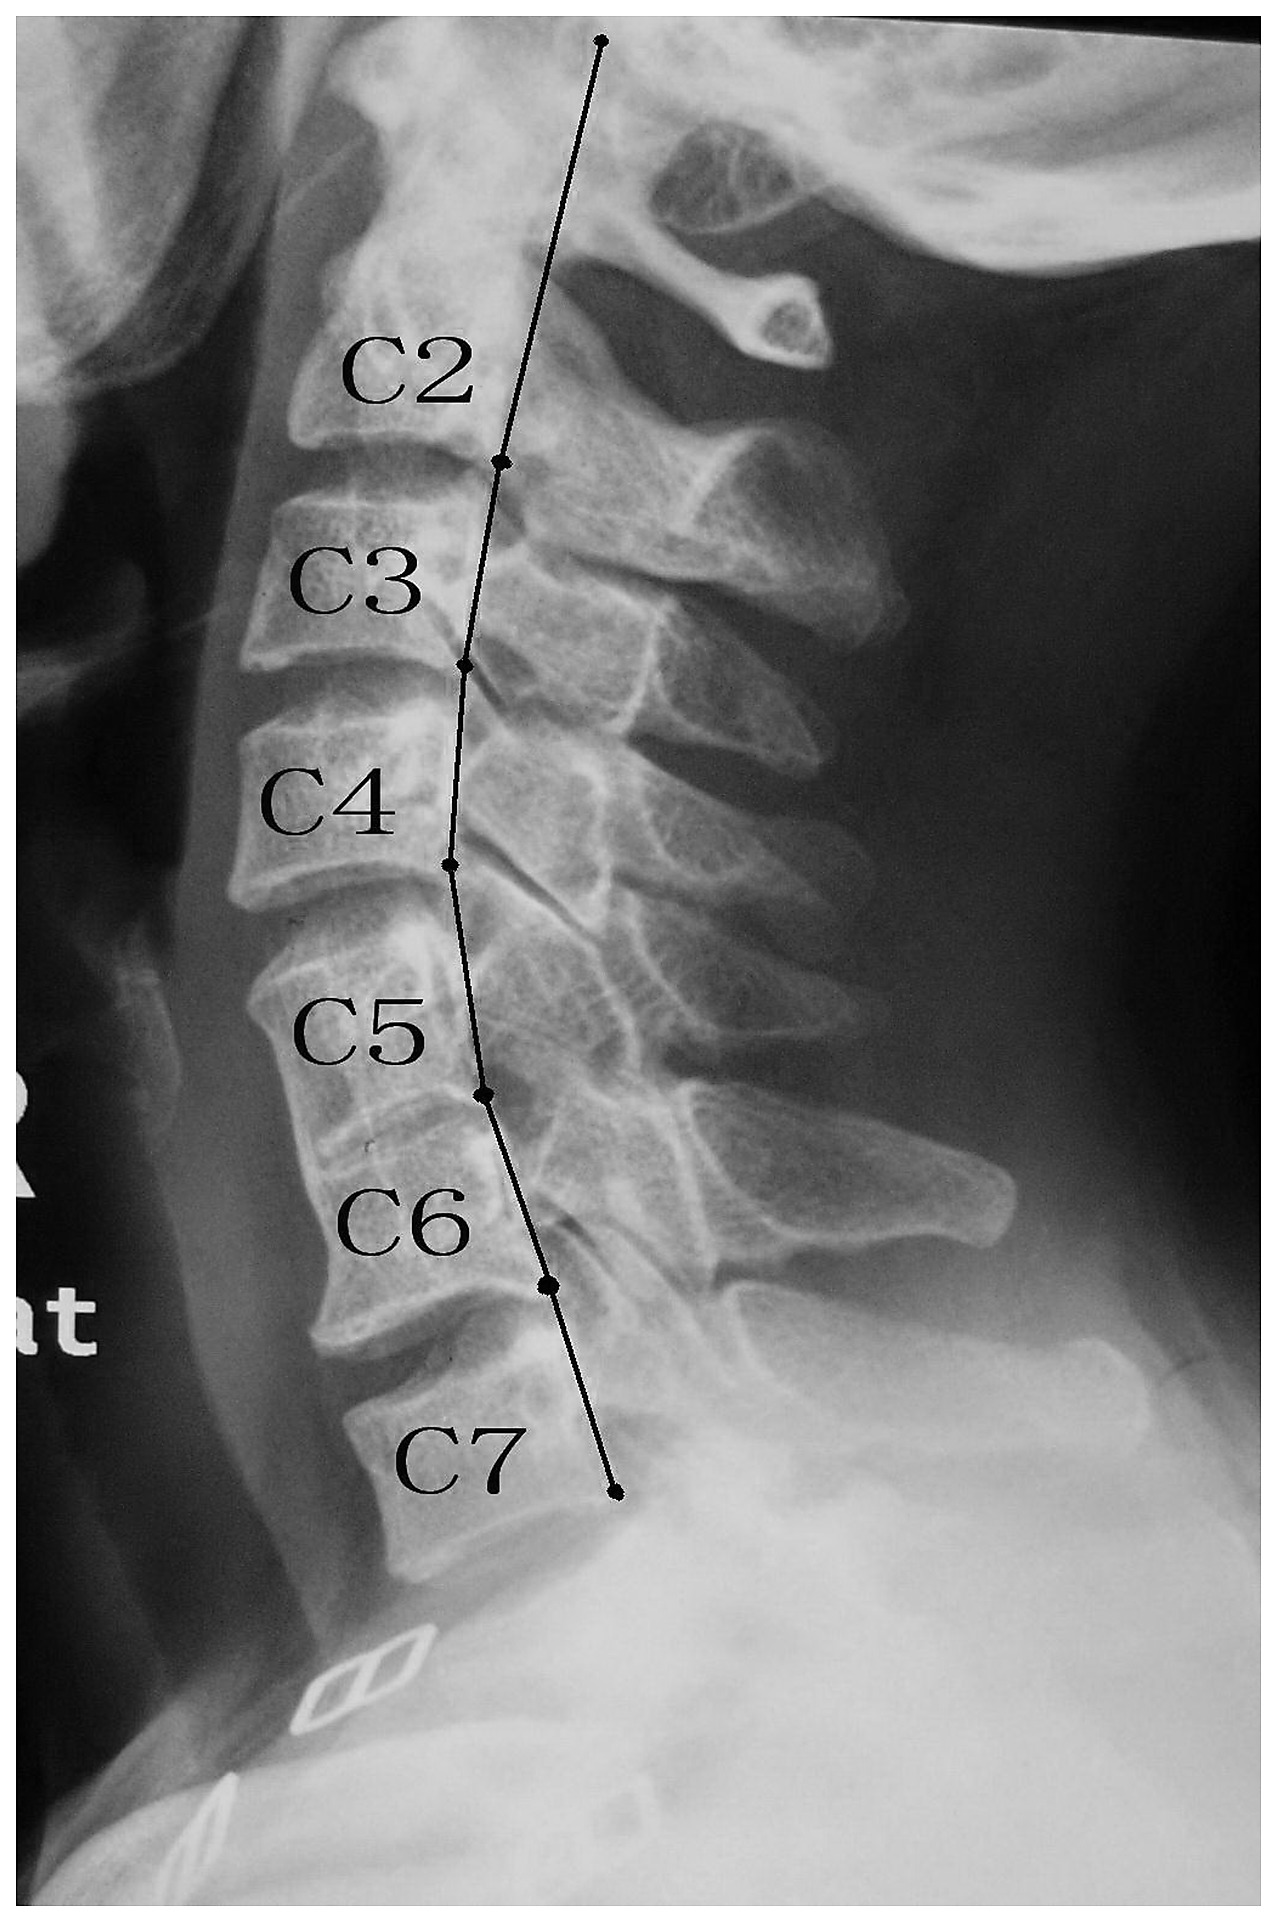

The name of this area of the vertebral column.

What is the cervical spine?